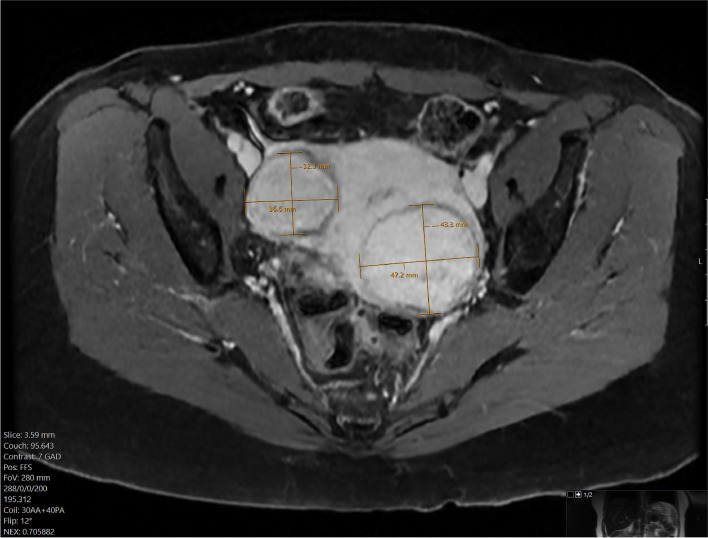

Methods: A 51 year old woman presenting with menorrhagia due to uterine fibroids was referred to interventional radiology for embolization. She was allergic to most opiates and had previously become agitated with IV midazolam, resulting in termination of a previous attempt at embolization. Thus, a combination of three analgesic modalities was used: intraarterial ropivacaine in the uterine arteries, superior hypogastric nerve block with ropivacaine, and intravenous acetaminophen. The patient underwent successful embolization and reported only intermittent pain of 1-2 out of 10 intensity.